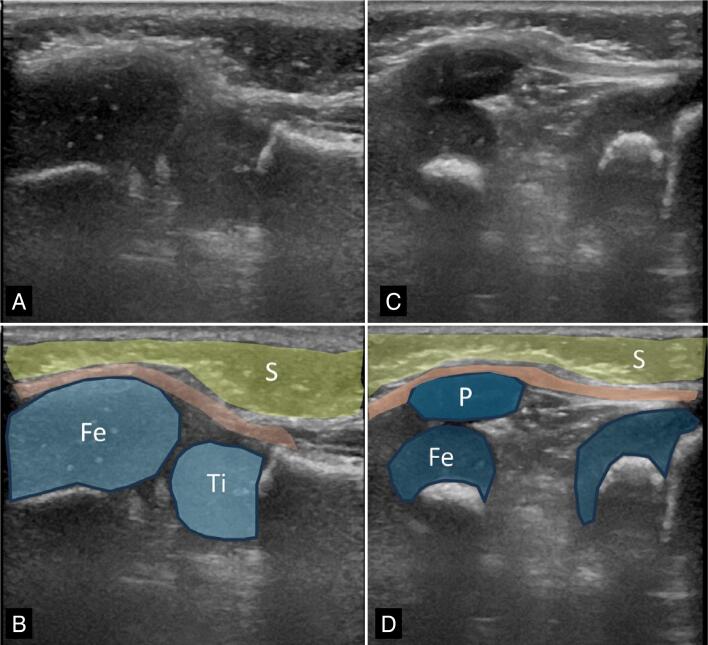

Objective: To analyze cases with clinical suspicion of patellar abnormalities, before ossification of the patella and to characterize the spectrum of abnormalities of the cartilaginous infantile patella by ultrasonography.

Results: Twelve patients with suspected patellar abnormalities were identified, with a mean age of 9 months and 4 days (±1.9 years), 75% male.

Findings: dislocation or subluxation associated with patellar hypoplasia (7 knees), low lying patella and patellar hypoplasia (2), unilateral patellar agenesis (1), bilateral patellar agenesis (1), patellar instability in dynamic assessment and absence of patellar morphological changes (1). In two patients, ultrasonography was negative. The craniocaudal diameter of the hypoplastic patellas measured 0.94 cm ± 0.24 cm and in the control group 1.24 cm and ±0.12 cm (p<0.01). The Insall-Salvati index adapted for ultrasonography measured 0.63±0.07 for the low lying patella and 0.93±0.16 in the control group (p=0.004).

Conclusions: Ultrasonography was useful to characterize abnormalities of the cartilaginous patella, and the most frequent findings were instability and hypoplasia. Level of Evidence IV; Case Series.